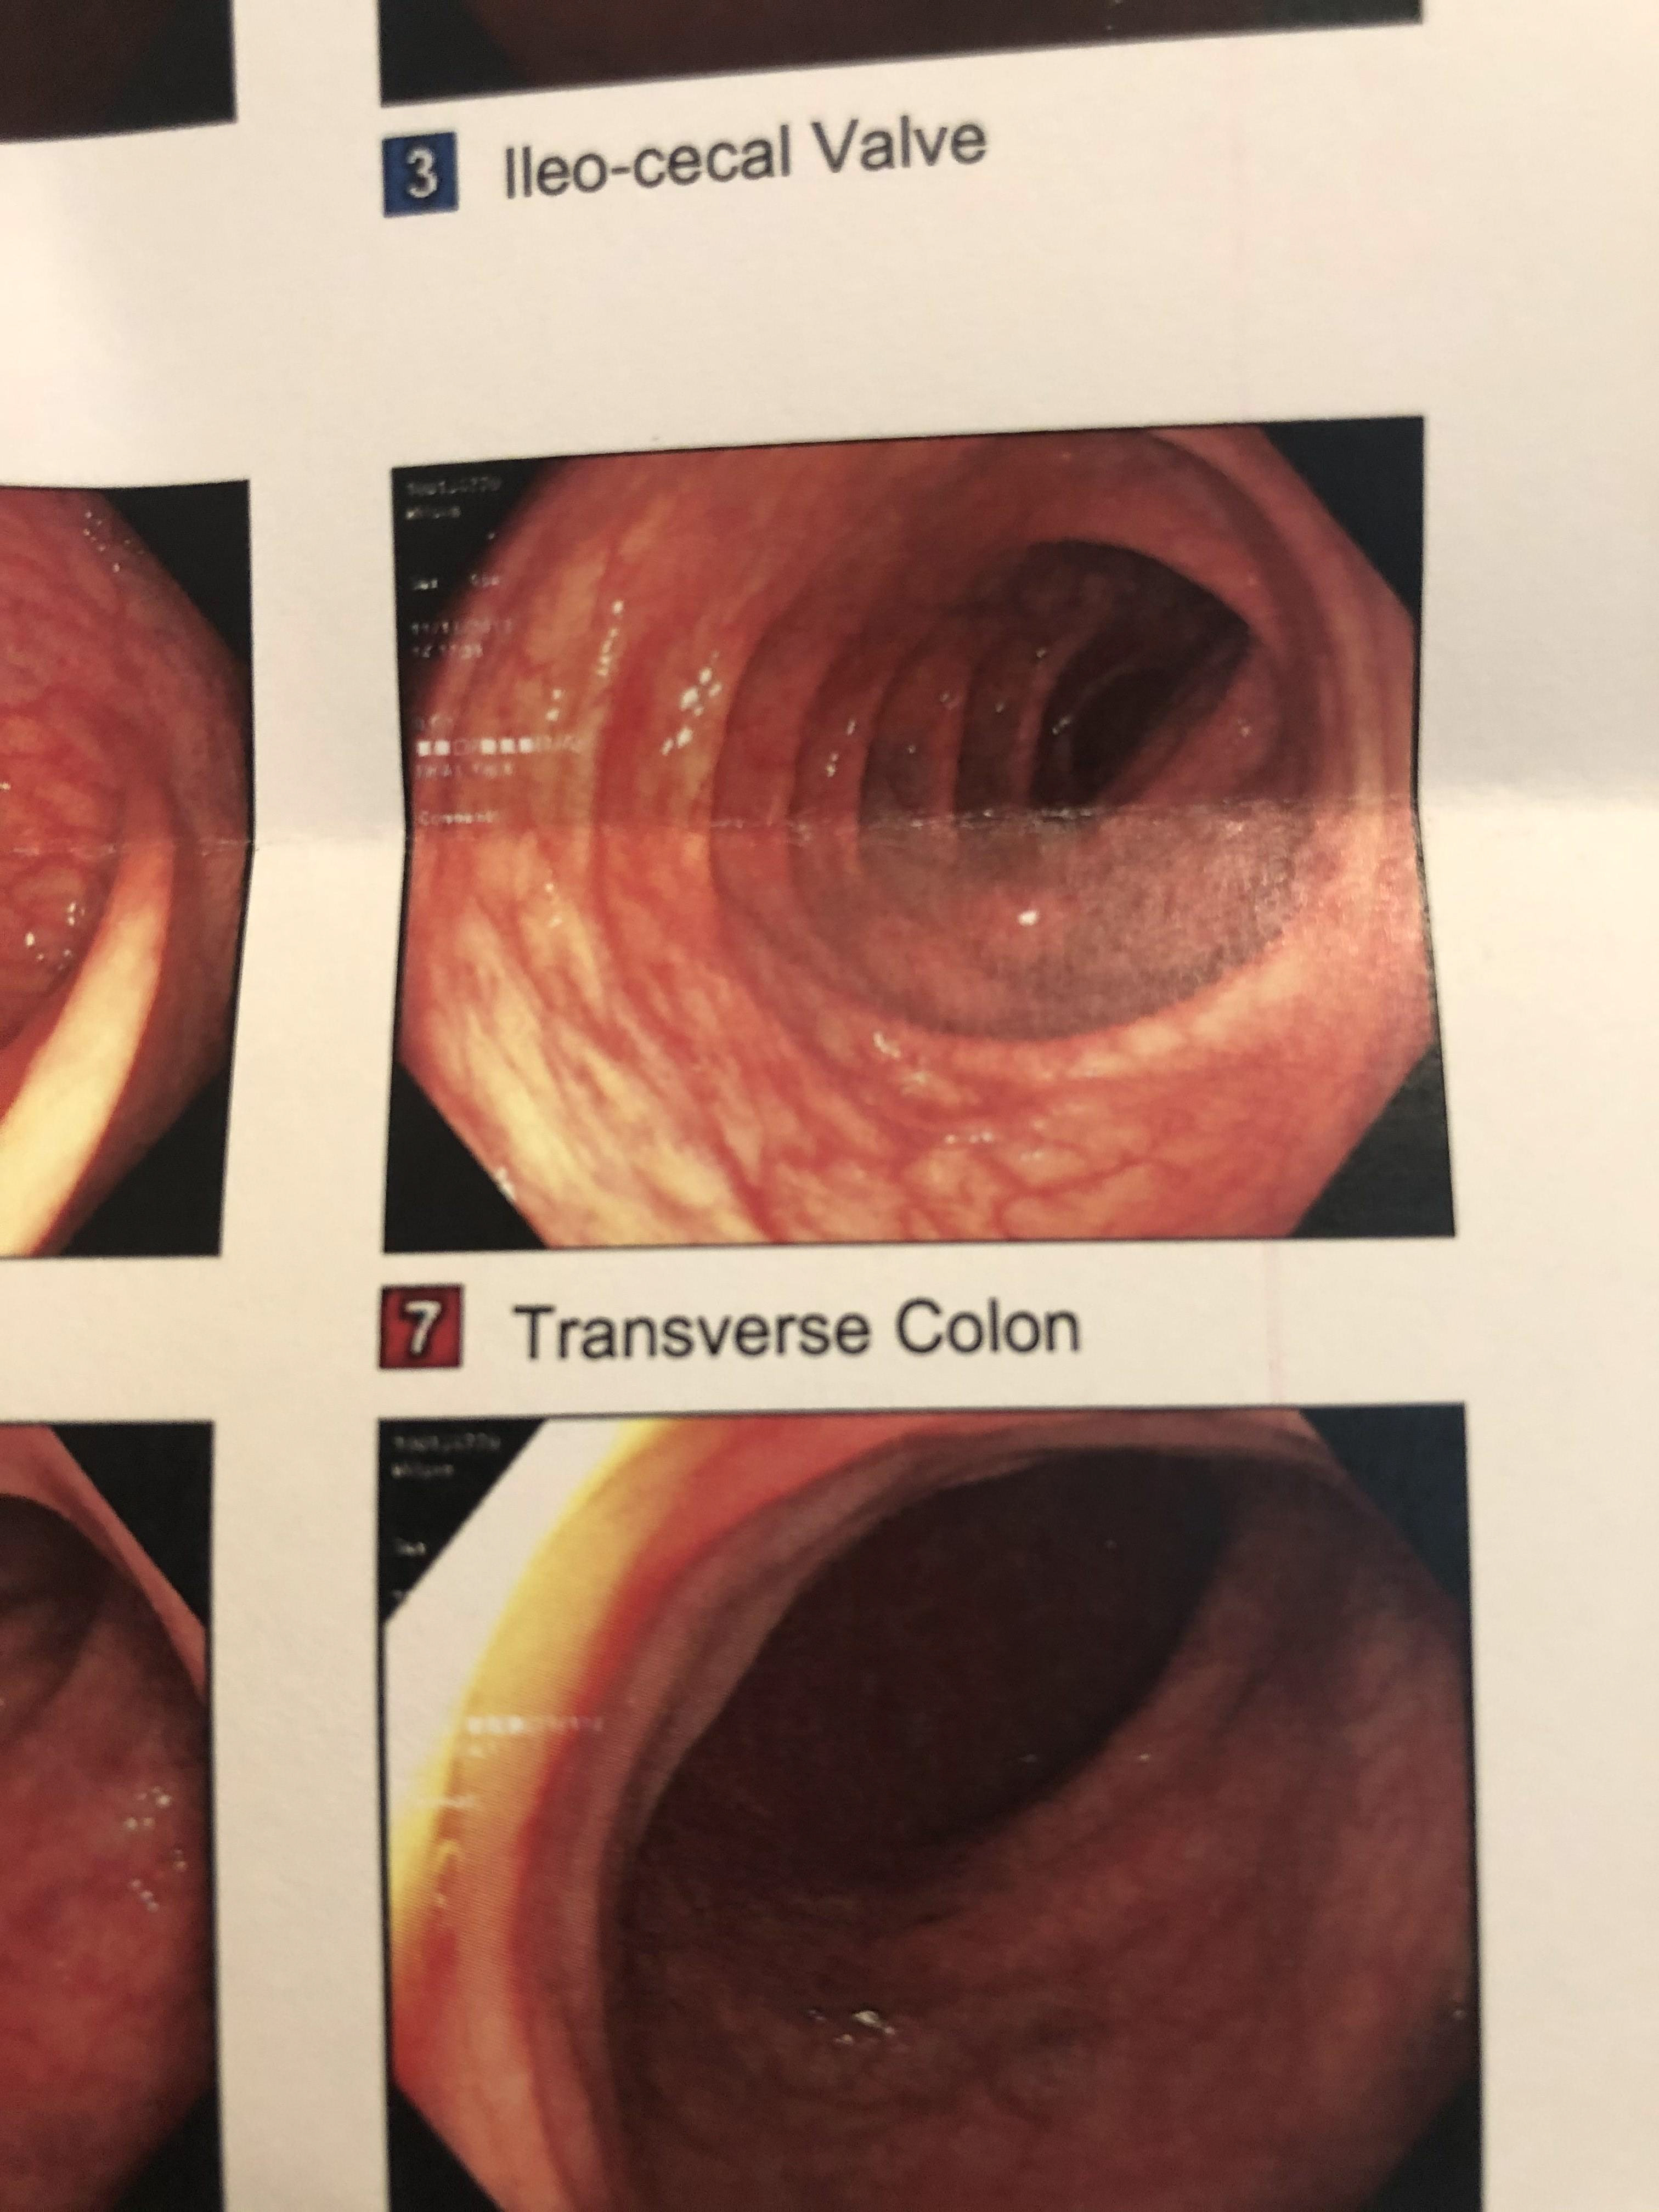

I developed a horrible anal fissure prior to my departure to Japan that made my experience in Naoshima indescribably painful. The goal of this study was to filter the experience of my anal fissure, realized as photos from a subsequent colonoscopy, through the parallel experience of Tadao Ando's structure.

Next, I created a simple collage of photos from my colonoscopy based on Chichu's topology.